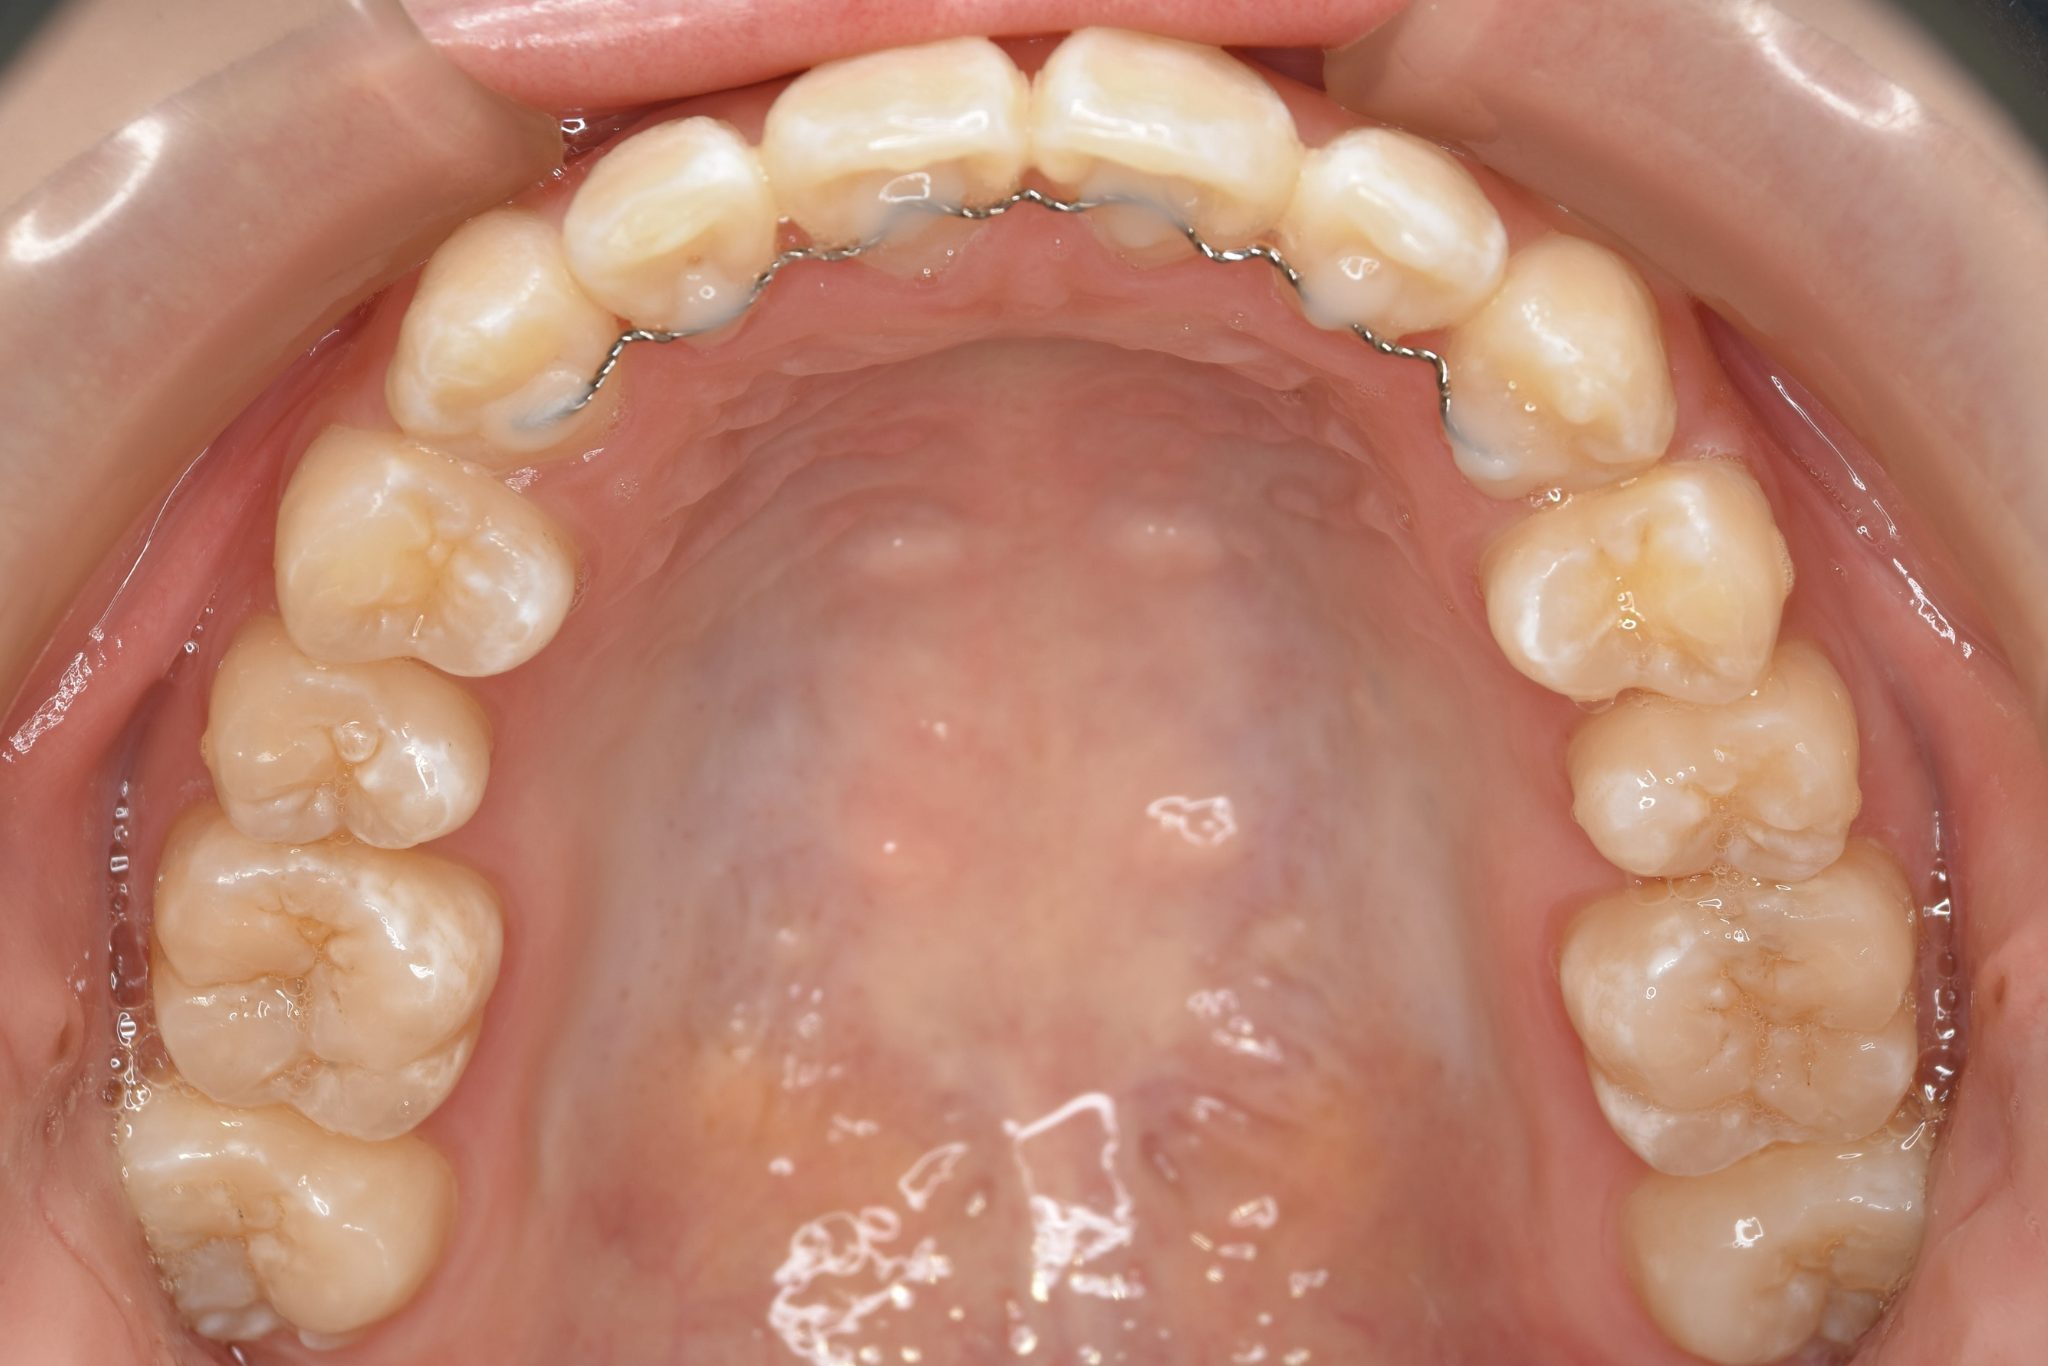

アフター

全顎ワイヤー矯正 症例_815

主訴 前歯の出っ歯|八重歯|下の歯のデコボコ|検診で噛み合わせが悪いと指摘されたこと

施術内容 成人矯正1期治療

治癒期間 1年4か月間

費用 954,800円(税込)